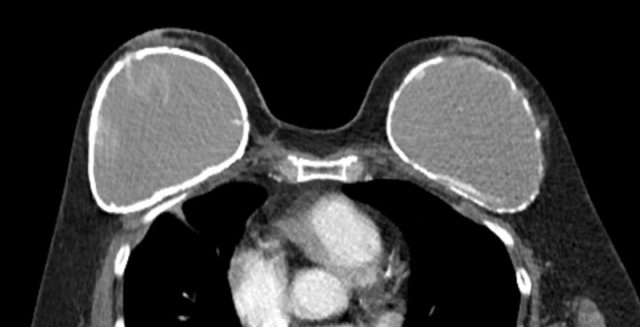

BIA-ALCL

Anaplastic Large Cell Lymphoma

BIA-ALCL or breast implant associated anaplastic large cell lymphoma is an important complication to know of silicon-filled and saline-filled breast implants.

BIA-ALCL develops primarily if not exclusively in patients with textured implants.

The estimated prevalence in these implants is 1:30.000.

Most BIA-ALCL were seen in Allergan Biocell textured breast implants and they were subsequently taken off the market.

Two-thirds of individuals with BIA-ALCL present with discomfort and swelling due to the development of periprosthetic effusion (85%) in which atypical lymphoid cells are found. Sometimes associated with a mass in 15% of cases.

Any late onset unilateral effusion or mass should be punctured and analyzed.

Staging is with PET-CT, like in any other lymphoma.

Most patients present with Stage 1.

The treatment is surgical excision of the implant, capsule and mass if present.

Outcome is favorable when early treated.